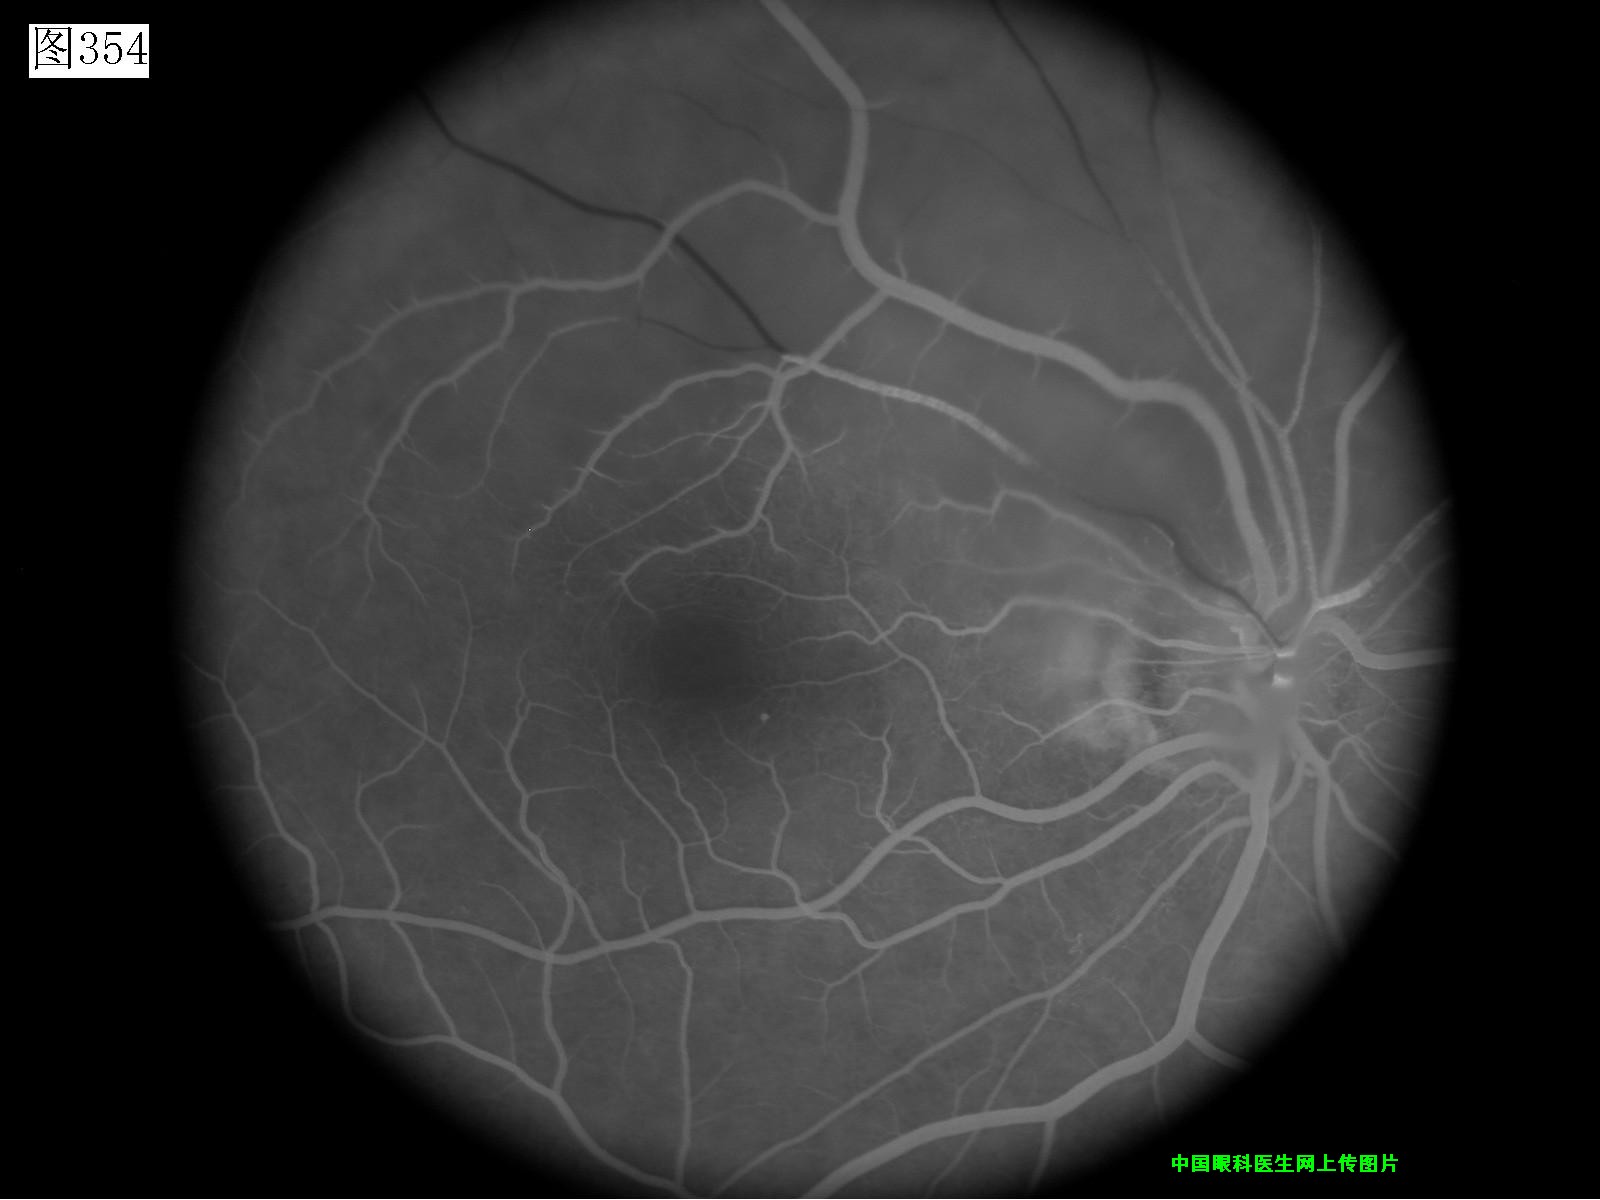

353 354 355 356